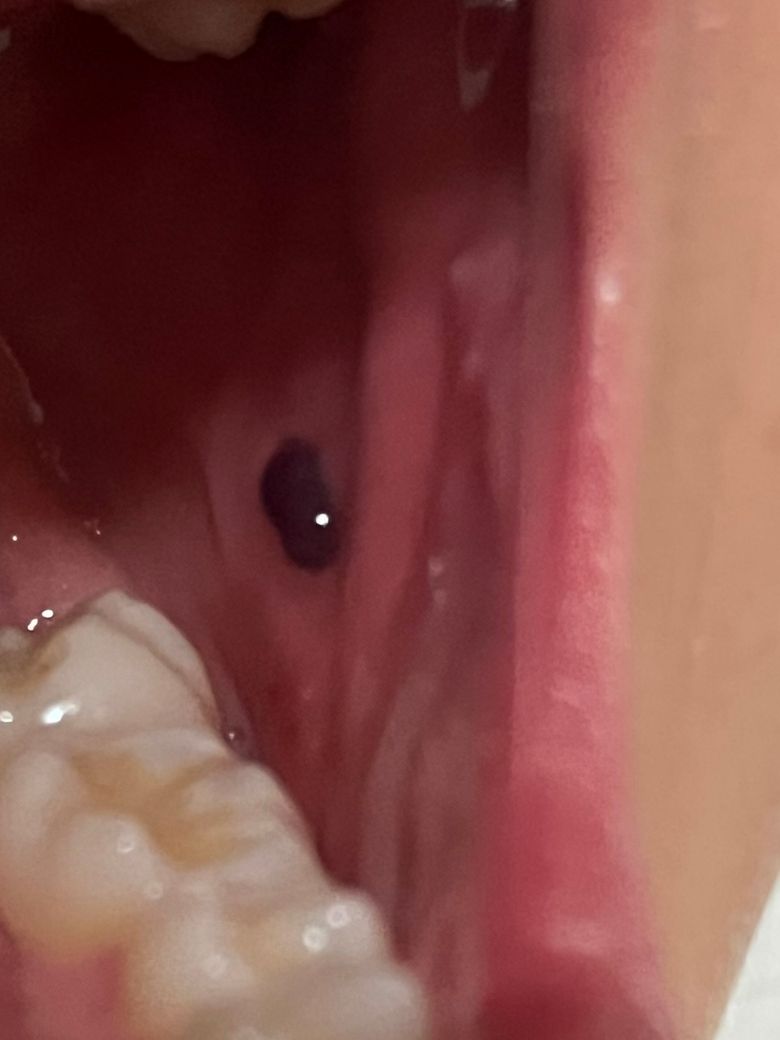

입 안 볼에 검정 혹 같은 게 생겼어요.

어제까지만 해도 없었던 거 같은데 통증도 없고요.

입 안에 이물감이 들어서 거울을 보고 발견했습니다.

• 사진상 병변은 볼 점막에 갑자기 생긴 검은색의 둥근 결절로 보이며, 통증이 없고 최근 발생했다는 점을 고려하면 가장 가능성이 높은 것은 점막하 출혈로 인한 혈종(혈액이 고인 상태)입니다. 평소 볼을 씹는 습관이 있다면 작은 혈관이 터지면서 이런 형태로 나타나는 경우가 흔합니다. 색이 짙은 자주색 또는 검은색으로 보이고, 단기간에 생기는 것이 특징입니다.

이 경우 대부분은 특별한 치료 없이 1에서 2주 사이에 자연 흡수되면서 점점 옅어지고 작아집니다. 억지로 터뜨리거나 건드리면 오히려 출혈이 더 생기거나 감염 위험이 있으므로 그대로 두는 것이 원칙입니다. 자극을 줄이고, 해당 부위를 씹지 않도록 주의하는 것이 중요합니다.

다만 몇 가지는 구분이 필요합니다. 크기가 점점 커지거나, 2주 이상 전혀 변화 없이 지속되는 경우, 표면이 딱딱하게 느껴지거나 불규칙한 형태로 변하는 경우는 단순 혈종이 아닐 수 있어 확인이 필요합니다. 드물게는 색소성 병변이나 혈관성 병변과 감별해야 합니다.

현재 상황에서는 급하게 치료가 필요한 소견은 아니며, 경과 관찰이 우선입니다. 진료가 필요하다면 치과 구강외과나 이비인후과에서 확인 가능합니다.